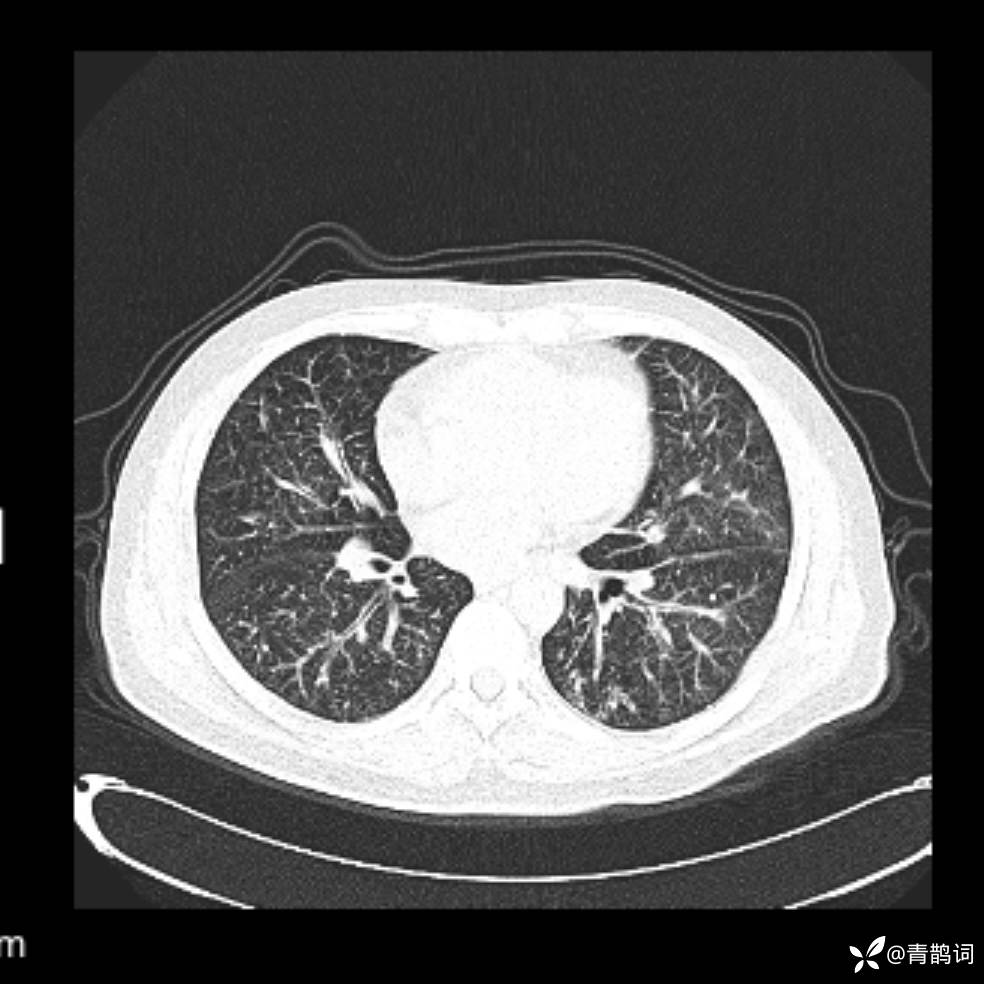

患者年龄:30岁。

患者性别:男。

简要病史:左颜面部肿胀2年,反复咳嗽咳痰,逐渐加重。

辅助检查

结合病史及影像学表现,期待评论区各位老师各抒己见~